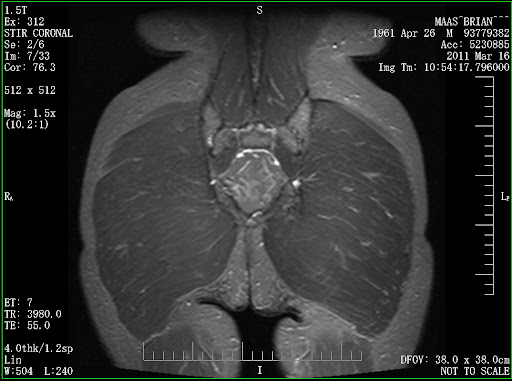

Here are my images of the pelvic stress fracture. I have to be honest, even though told that these two images best show my fracture in the left pelvis, I can't really see what I am looking for! But I said I would share images when I got them. Maybe someone with a bit more experience can see them: